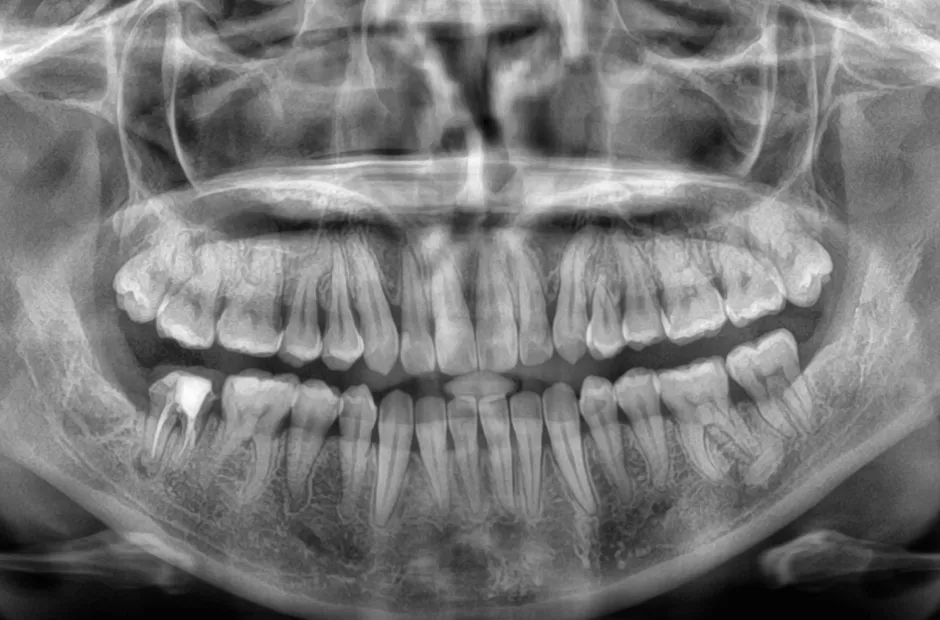

過剰歯

| 診断名・主訴 | でこぼこ |

|---|---|

| 年齢・性別 | 22歳・女性 |

| 治療期間・回数 | 1年6か月 |

| 治療に用いた主な装置 | リンガルブラケット |

| 抜歯部位 | 過剰歯 |

| 治療費 | 100万円(税抜) |

| リスク・副作用 | 装置による違和感・疼痛・歯肉退縮・歯根吸収・虫歯のリスクなど |

治療前